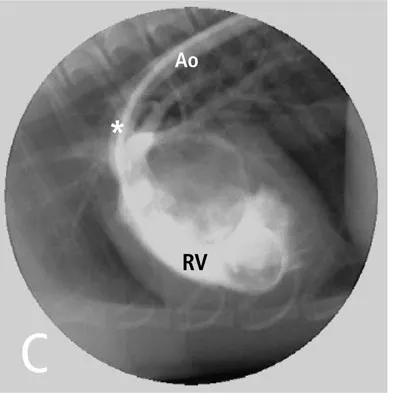

Finally, with reverse patent ductus arteriosus, only the caudal mucous membranes will be cyanotic because the brachycephalic trunk and left subclavian, which supply blood to the head and thoracic limbs, arise proximal to the site of right-sided blood entry (Figure C). This right ventricular angiogram demonstrates blood flow from the right ventricle (RV) crossing the patent ductus arteriosus (*) and into the distal aorta (Ao) in a dog with reverse patent ductus arteriosus. Note that the venous blood from the right ventricle enters the descending thoracic aorta after the origins of the brachycephalic trunk and left subclavian arteries.